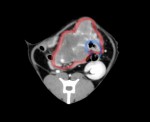

レントゲン検査およびエコー検査を実施したところ、上腹部に直径約6.5cm大の巨大な腫瘤と胸腔内にも腫瘤を認めた。

後日精査するためにCT検査およびFNA検査を実施し、消化管型リンパ腫と診断できた。胸腔内の腫瘤は胸骨リンパ節の腫大と考えられ、その他のリンパ節も多数腫大していることが分かった。現在、化学療法を実施中である。治療後1週間の腫瘤は、腹部触診では殆ど触知できないまで縮小し、生活の質は向上している。